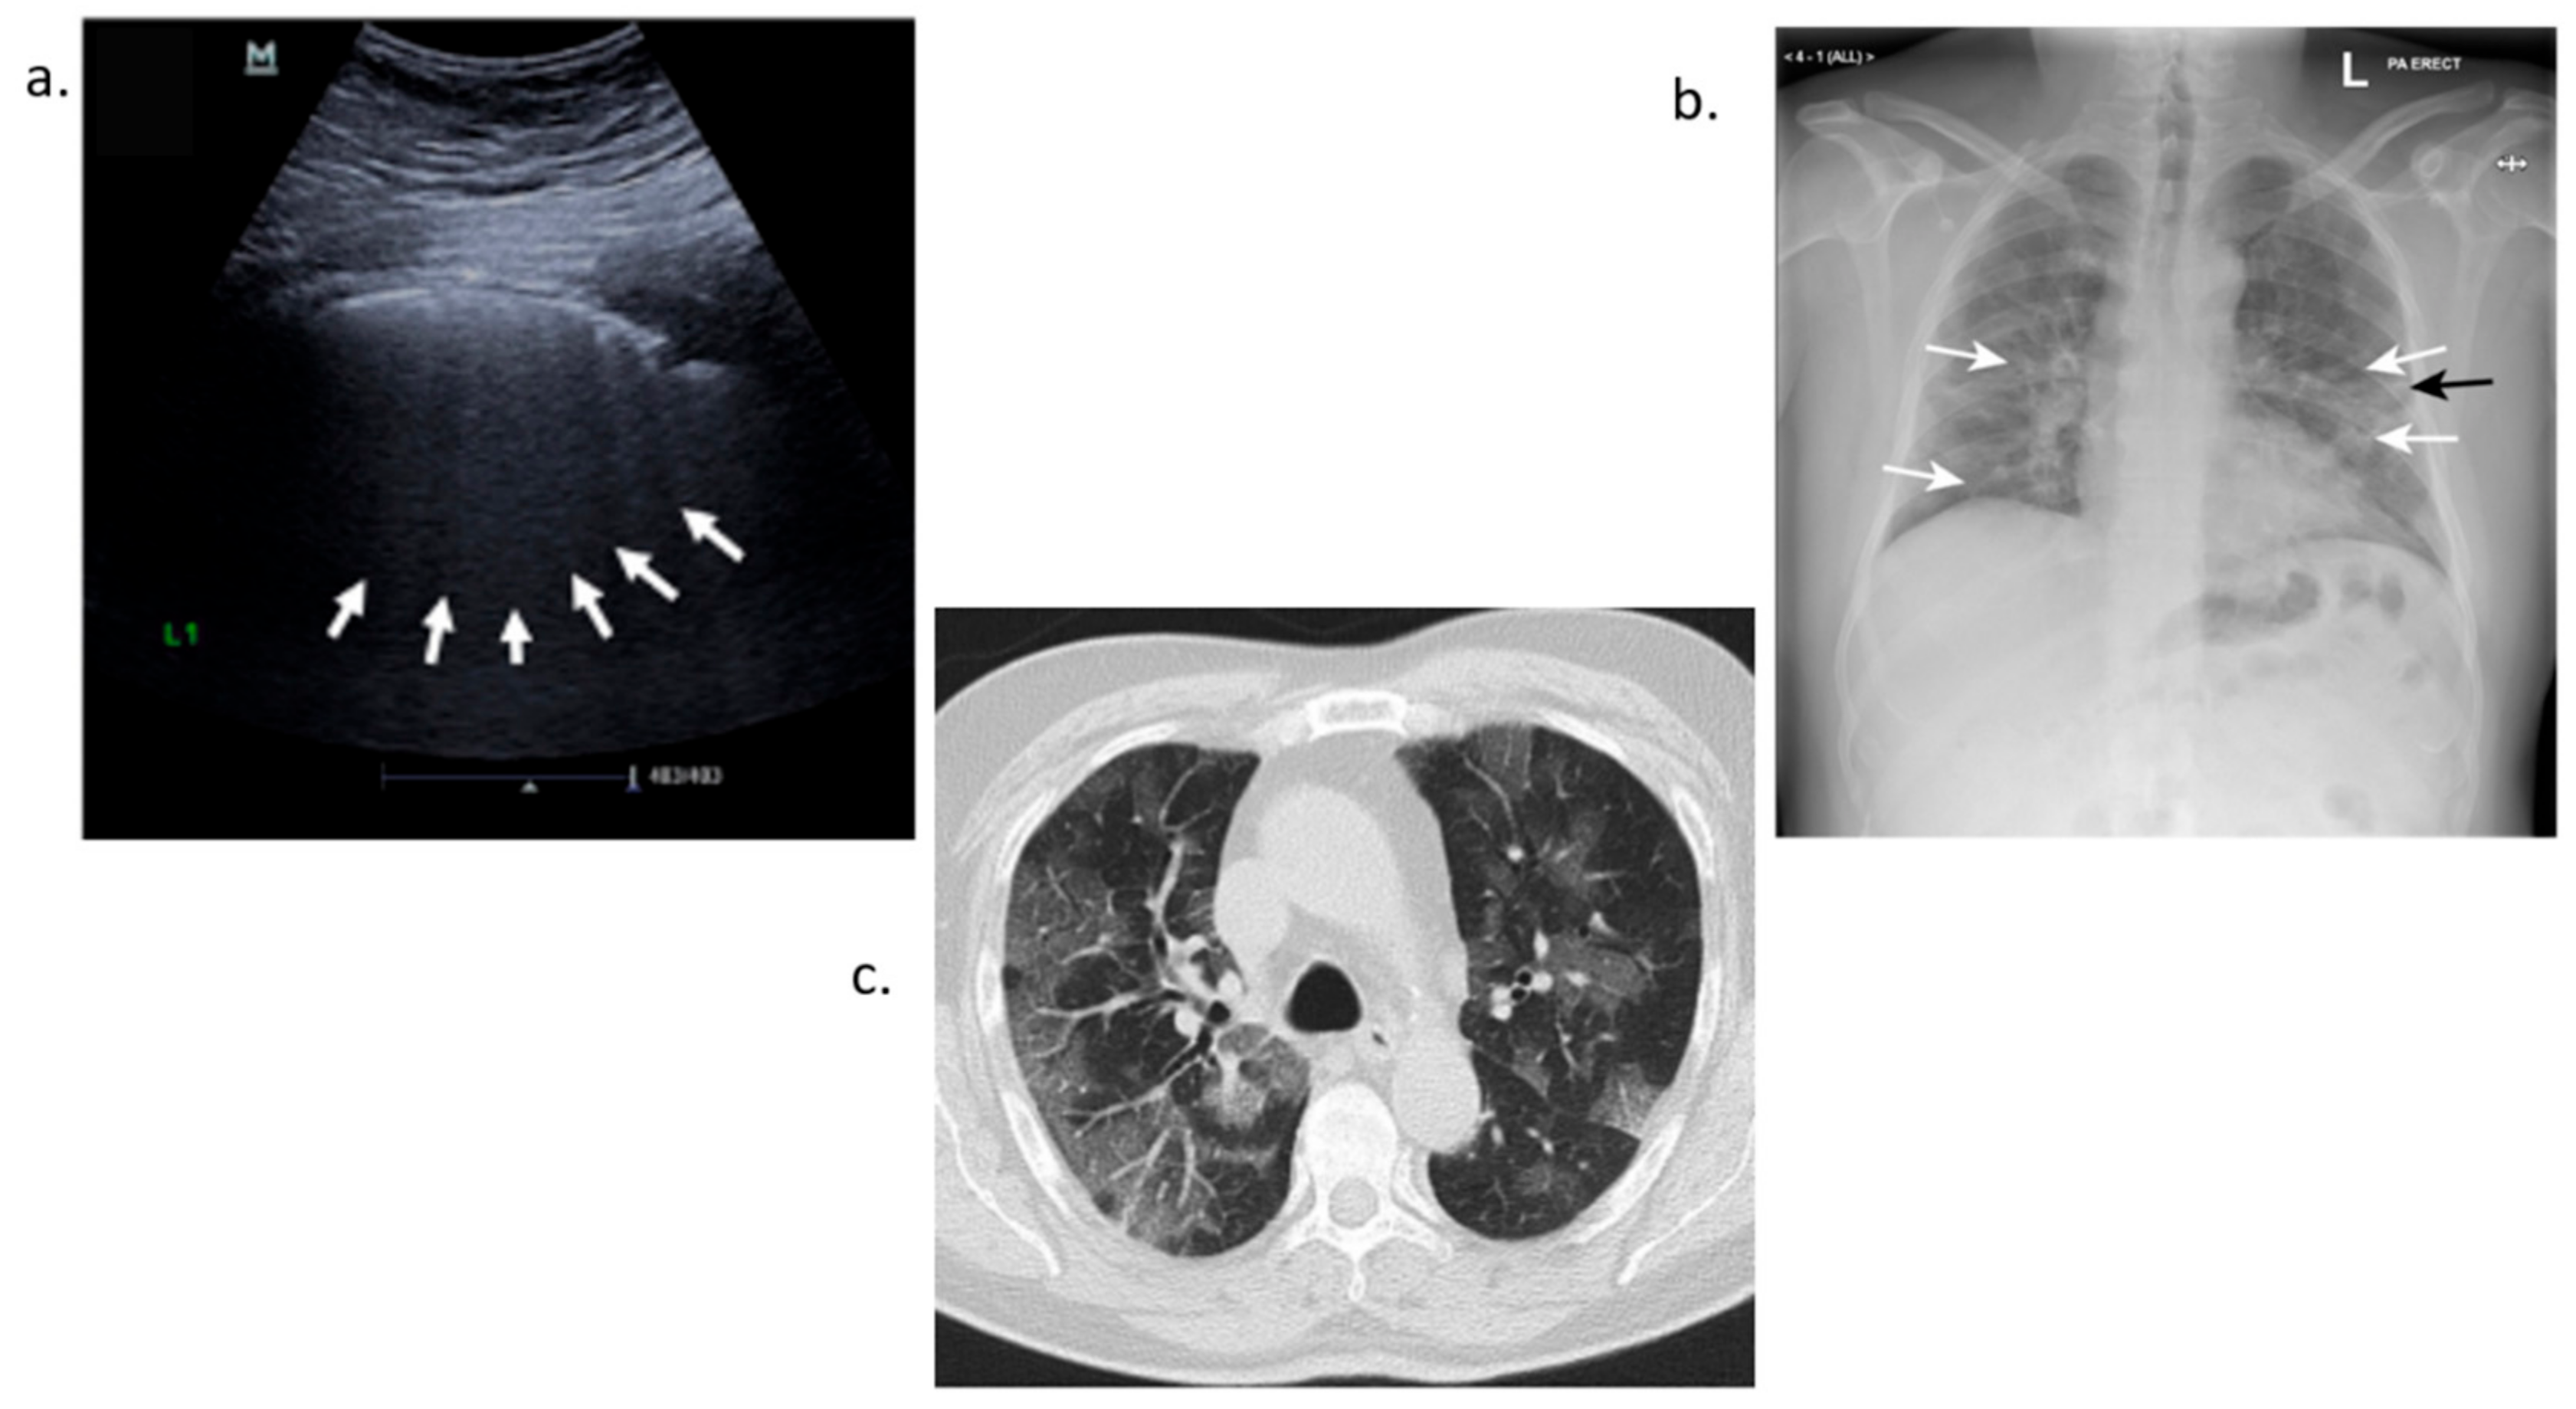

3.4.1. Ultrasound Detection

3.4.2. X-ray Detection

3.4.3. Computerized Tomography Scan-CT Scan Detection

- Buda, N.; Grau, E.S.; Cylwik, J.; Welnicki, M. Lung Ultrasound in the diagnosis of COVID-19 infection—A case series and review of the literature. Adv. Med. Sci. 2020, 2, 318–385. [Google Scholar] [CrossRef]

- Jackson, K.; Butler, R.; Aujayeb, A. Lung ultrasound in the COVID-19 pandemic. Postgrad. Med. J. 2021, 97, 34–39. [Google Scholar] [CrossRef] [PubMed]

- Jacobi, A.; Chung, M.; Bernheim, A.; Eber, C. Portable chest X-ray in coronavirus disease-19 (COVID-19): A pictorial review. Clin. Imaging 2020, 64, 35–42. [Google Scholar] [CrossRef]

- Ng, M.-Y.; Lee, E.Y.P.; Yang, J.; Yang, F.; Li, X.; Wang, H.; Lui, M.M.-S.; Lo, C.S.-Y.; Leung, B.; Khong, P.-L.; et al. Imaging Profile of the COVID-19 Infection: Radiologic Findings and Literature Review. Radiol. Cardiothorac. Imaging 2020, 2, e200034. [Google Scholar] [CrossRef]